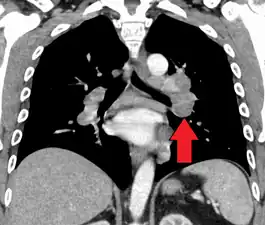

Hilar adenopathy especially on the person's left (coronal CT)

Hilar adenopathy especially on the person's left (transverse CT)